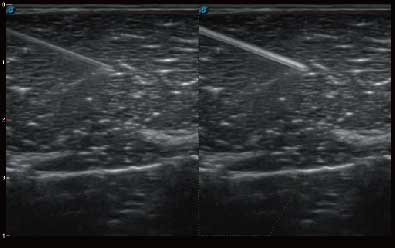

• 弹性成像

全新算法处理射频信号 不可靠区域自动剔除 支持定量分析 压力曲线保证重复性

• 穿刺增强

自动识别穿刺针进行声束智能偏转 手动修正多档调节 提高一次穿刺成功率